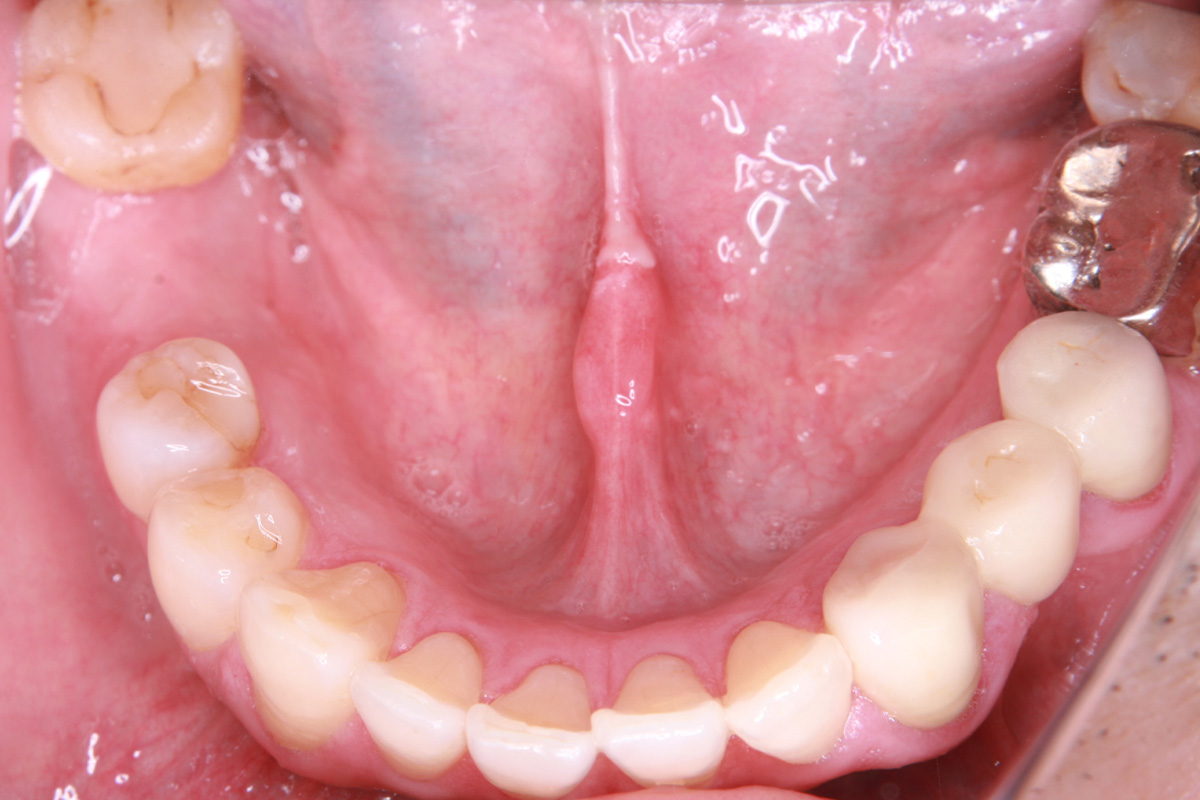

初診時

歯が割れていて、痛みがあり、抜歯となりました。

パノラマレントゲン写真 -